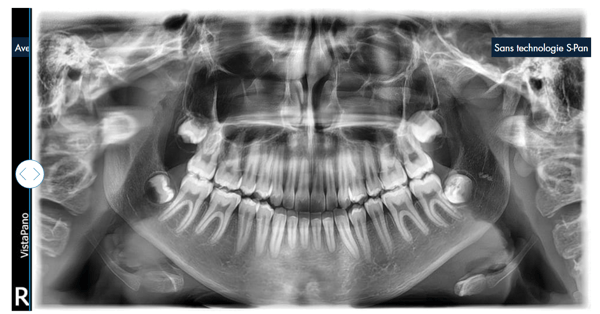

La technologie S-Pan : des images d'une netteté exceptionnelle pour des diagnostics sûrs

Contrairement à la méthode traditionnelle, la technologie S-Pan sélectionne automatiquement, parmi de nombreuses couches parallèles, les sections d’image qui représentent le mieux l’anatomie individuelle du patient. Lors de l’assemblage de l’image panoramique, les écarts par rapport à la « dentition moyenne » sont également pris en compte, tout comme l’inclinaison individuelle des dents. On obtient, par conséquent, une image d’une clarté exceptionnelle qui permet au dentiste de trouver immédiatement les structures pertinentes. Comme la reconstruction s'oriente en fonction de la situation effective de la dentition, les erreurs de positionnement sont « compensées » dans certaines limites. Ainsi, le cabinet gagne du temps, et le client ne subit aucune répétition de clichés.

Comparaison de la technologie S-Pan